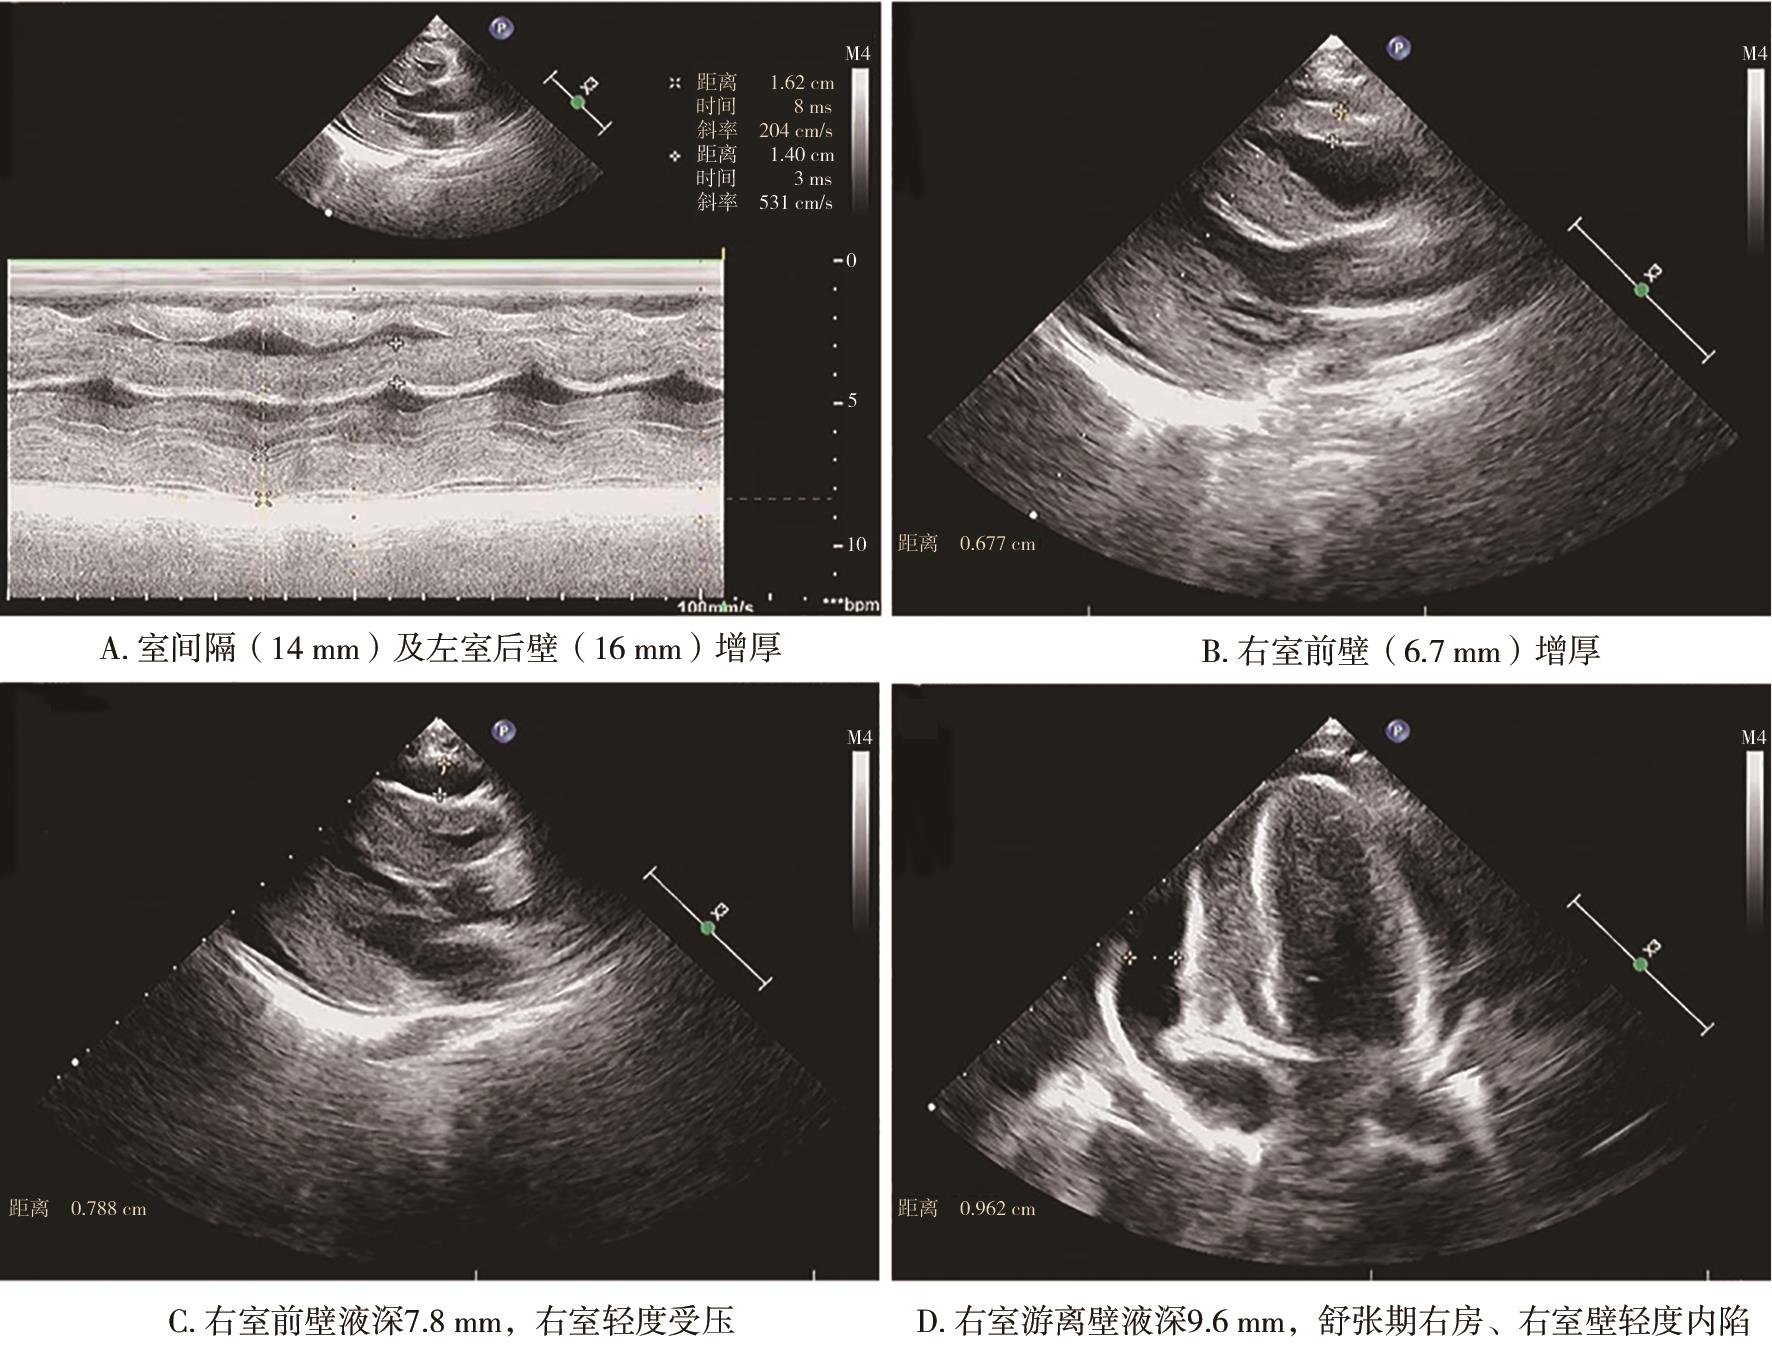

• 儿童横纹肌溶解症合并心包填塞、心肌肥厚1例报道

2023, 48(3):362-365. DOI: 10.13406/j.cnki.cyxb.003034

摘要 (107) HTML (36) PDF 9.91 M (361) 评论 (0) 收藏